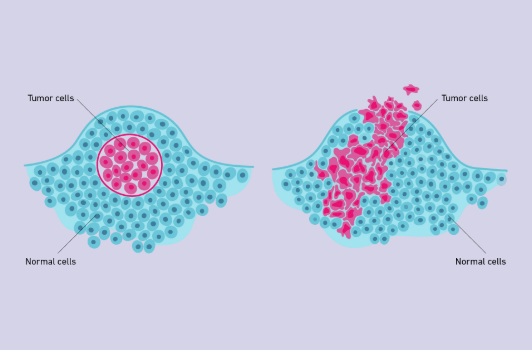

Benign Tumor

A tumor that does not affect surrounding tissues other than by physically crowding them (Left)

Malignant Tumor

A tumor that interferes with the functioning of surrounding cells; a cancerous tumor (Right)